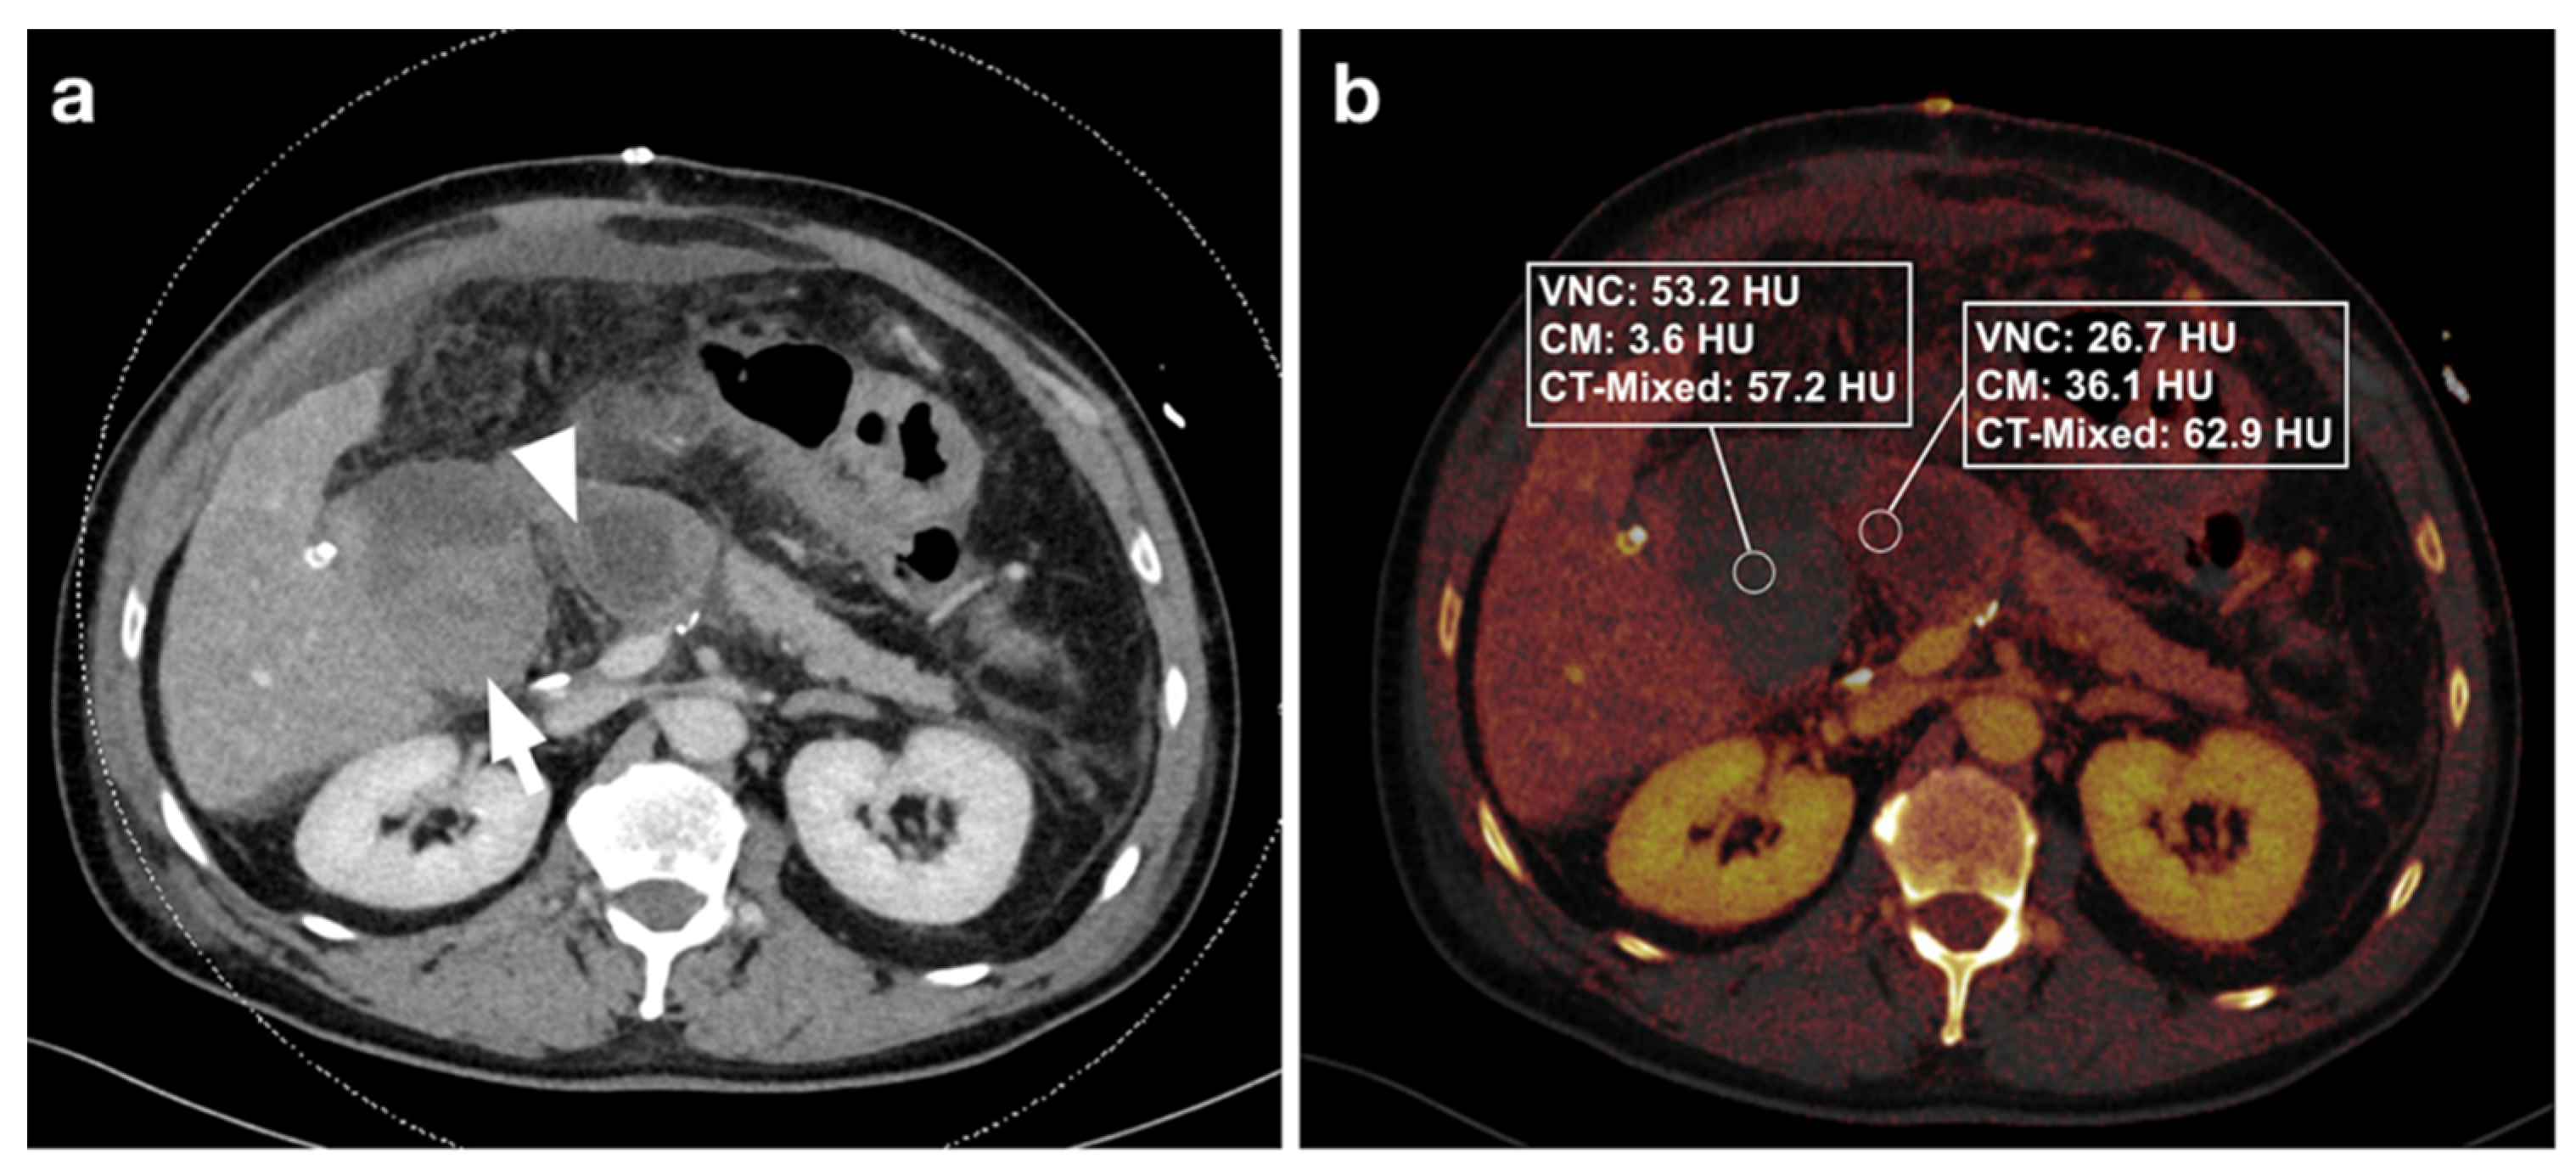

3.2.1. DECT Image Analysis